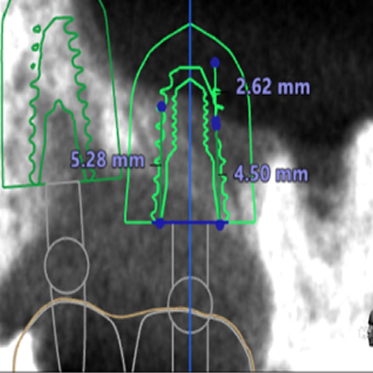

● 上の顎の奥歯にインプラントを入れるのに骨が足りないため、ソケットリフトと人工骨補填して骨造成を行った症例1

術前

藤沢デンタルオフィスのインプラント術前 藤沢デンタルオフィスのインプラント術前

3Dシミュレーション

術後

藤沢デンタルオフィスのインプラント術後 藤沢デンタルオフィスのインプラント術後

シミュレーション通りの上顎洞底挙上と人工骨補填(3Dガイドシステム使用)

● 上の顎の奥歯にインプラントを入れるのに骨が足りないため、ソケットリフトと人工骨補填して骨造成を行った症例2